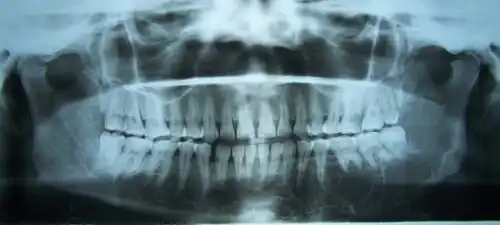

Radiograficamente, é uma lesão sempre radiolúcida, uni ou multilocular, que pode ser bem delimitada ou difusa. Nas lesões multiloculares, observa-se presença de septos ósseos em padrão de bolha de sabão (favo de mel) ou de raquete de tênis.[3]

Além do exame clínico, exames de imagem como radiografias panorâmicas e tomografias computadorizadas são utilizadas para fins diagnósticos e planejamento cirúrgico.[2][3] A biópsia é obrigatória para confirmação do diagnóstico.[3]